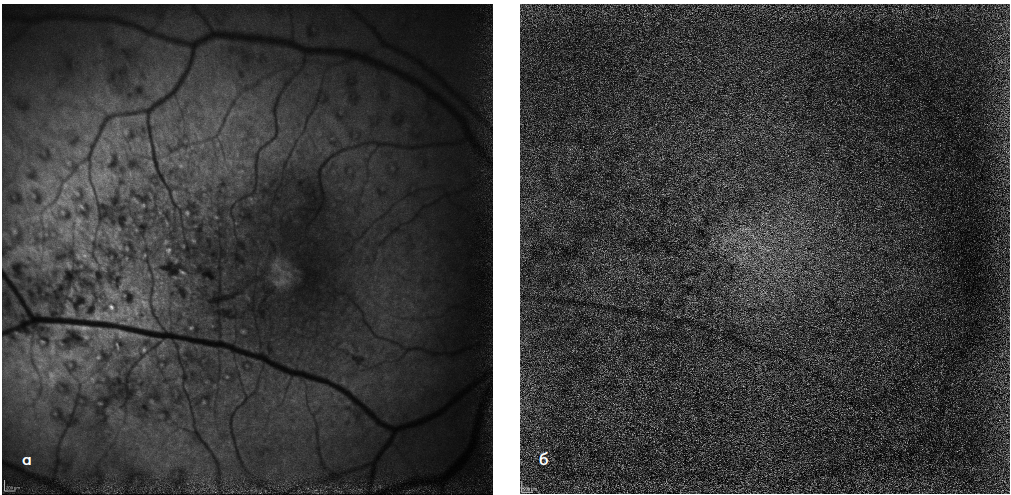

Клиническую оценку безопасности технологии комбинированного лазерного лечения ДМО проводили на основе данных аутофлюоресценции (АФ) в коротковолновом и инфракрасном режимах, а также показателей СЧ по результатам компьютерной микропериметрии. Так, в срок наблюдения 1 месяц было отмечено образование точечных очагов лазериндуцированного повреждения слоя РПЭ (гипер-АФ) в участках, соответствующих зонам порогового лазерного воздействия. В фовеальной аваскулярной зоне, где проводилось только СМЛВ, подобных изменений выявлено не было (рис. 1 а, б). При сравнении АФ-картины в динамике признаков дополнительного повреждения слоя РПЭ в результате повторных сеансов СМЛВ не было выявлено ни в одном из случаев (рис. 2 а, б). По данным компьютерной микропериметрии, в течение всего срока наблюдения образования абсолютных скотом в зонах лазерного воздействия также не наблюдалось во всех случаях (рис. 3 а, б).

Рис. 1. АФ-картина глазного дна пациентки Ц. в коротковолновом (а) и инфракрасном (б) режимах в срок 1 месяц от начала лечения. Точечные очаги гипер-(а) и гипофлюоресценции (б) соответствуют зонам лазеркоагуляции по площади макулярного отека. В фовеальной аваскулярной зоне признаки лазериндуцированных повреждений отсутствуют.

Рис. 2. АФ-картина глазного дна той же пациентки в срок 12 месяцев в коротковолновом (а) и инфракрасном (б) режимах. Проведено 2 дополнительных сеанса СМЛВ по всей зоне ретинального отека, увеличения степени лазериндуцированного повреждения не выявлено.